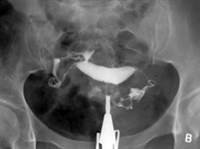

Гистеросальпингография — специальный рентгеноконтрастный метод исследования, используемый в гинекологической практике для выявления проходимости маточных труб, определения анатомических изменений в полости матки, спаечного процесса в малом тазу. При этом полость матки заполняют рентгеноконтрастным веществом и выполняют рентгенологическое исследование. В результате врач получает четкое изображение контуров матки и маточных труб, а свободное поступление контраста в брюшную полость свидетельствует об их проходимости.

В норме на гистеросальпингограмме полость матки имеет треугольную форму, маточные трубы на всем протяжении заполнены контрастным веществом, которое свободно поступает в брюшную полость. Для проведения гистеросальпингографии в настоящее время используют воднорастворимые контрастные вещества (верографин, уротраст). Эти вещества, благодаря своим структурным особенностям, дают более четкое изображение щелей, лакун, выбуханий в стенках матки (по сравнению с масляными контрастами, применявшимися раньше), а также лучше контрастируют спайки в полости малого таза, что имеет важное диагностическое значение для выявления внутреннего эндометриоза (аденомиоза), небольших миоматозных узлов и полипов эндометрия.